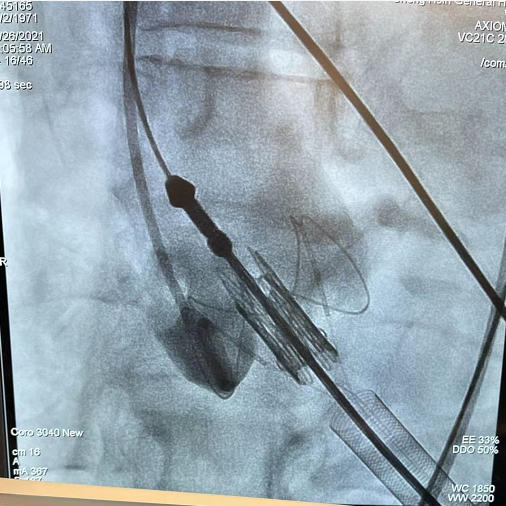

释放瓣膜后,瓣膜位置和形态理想

造影确认无反流和瓣周漏